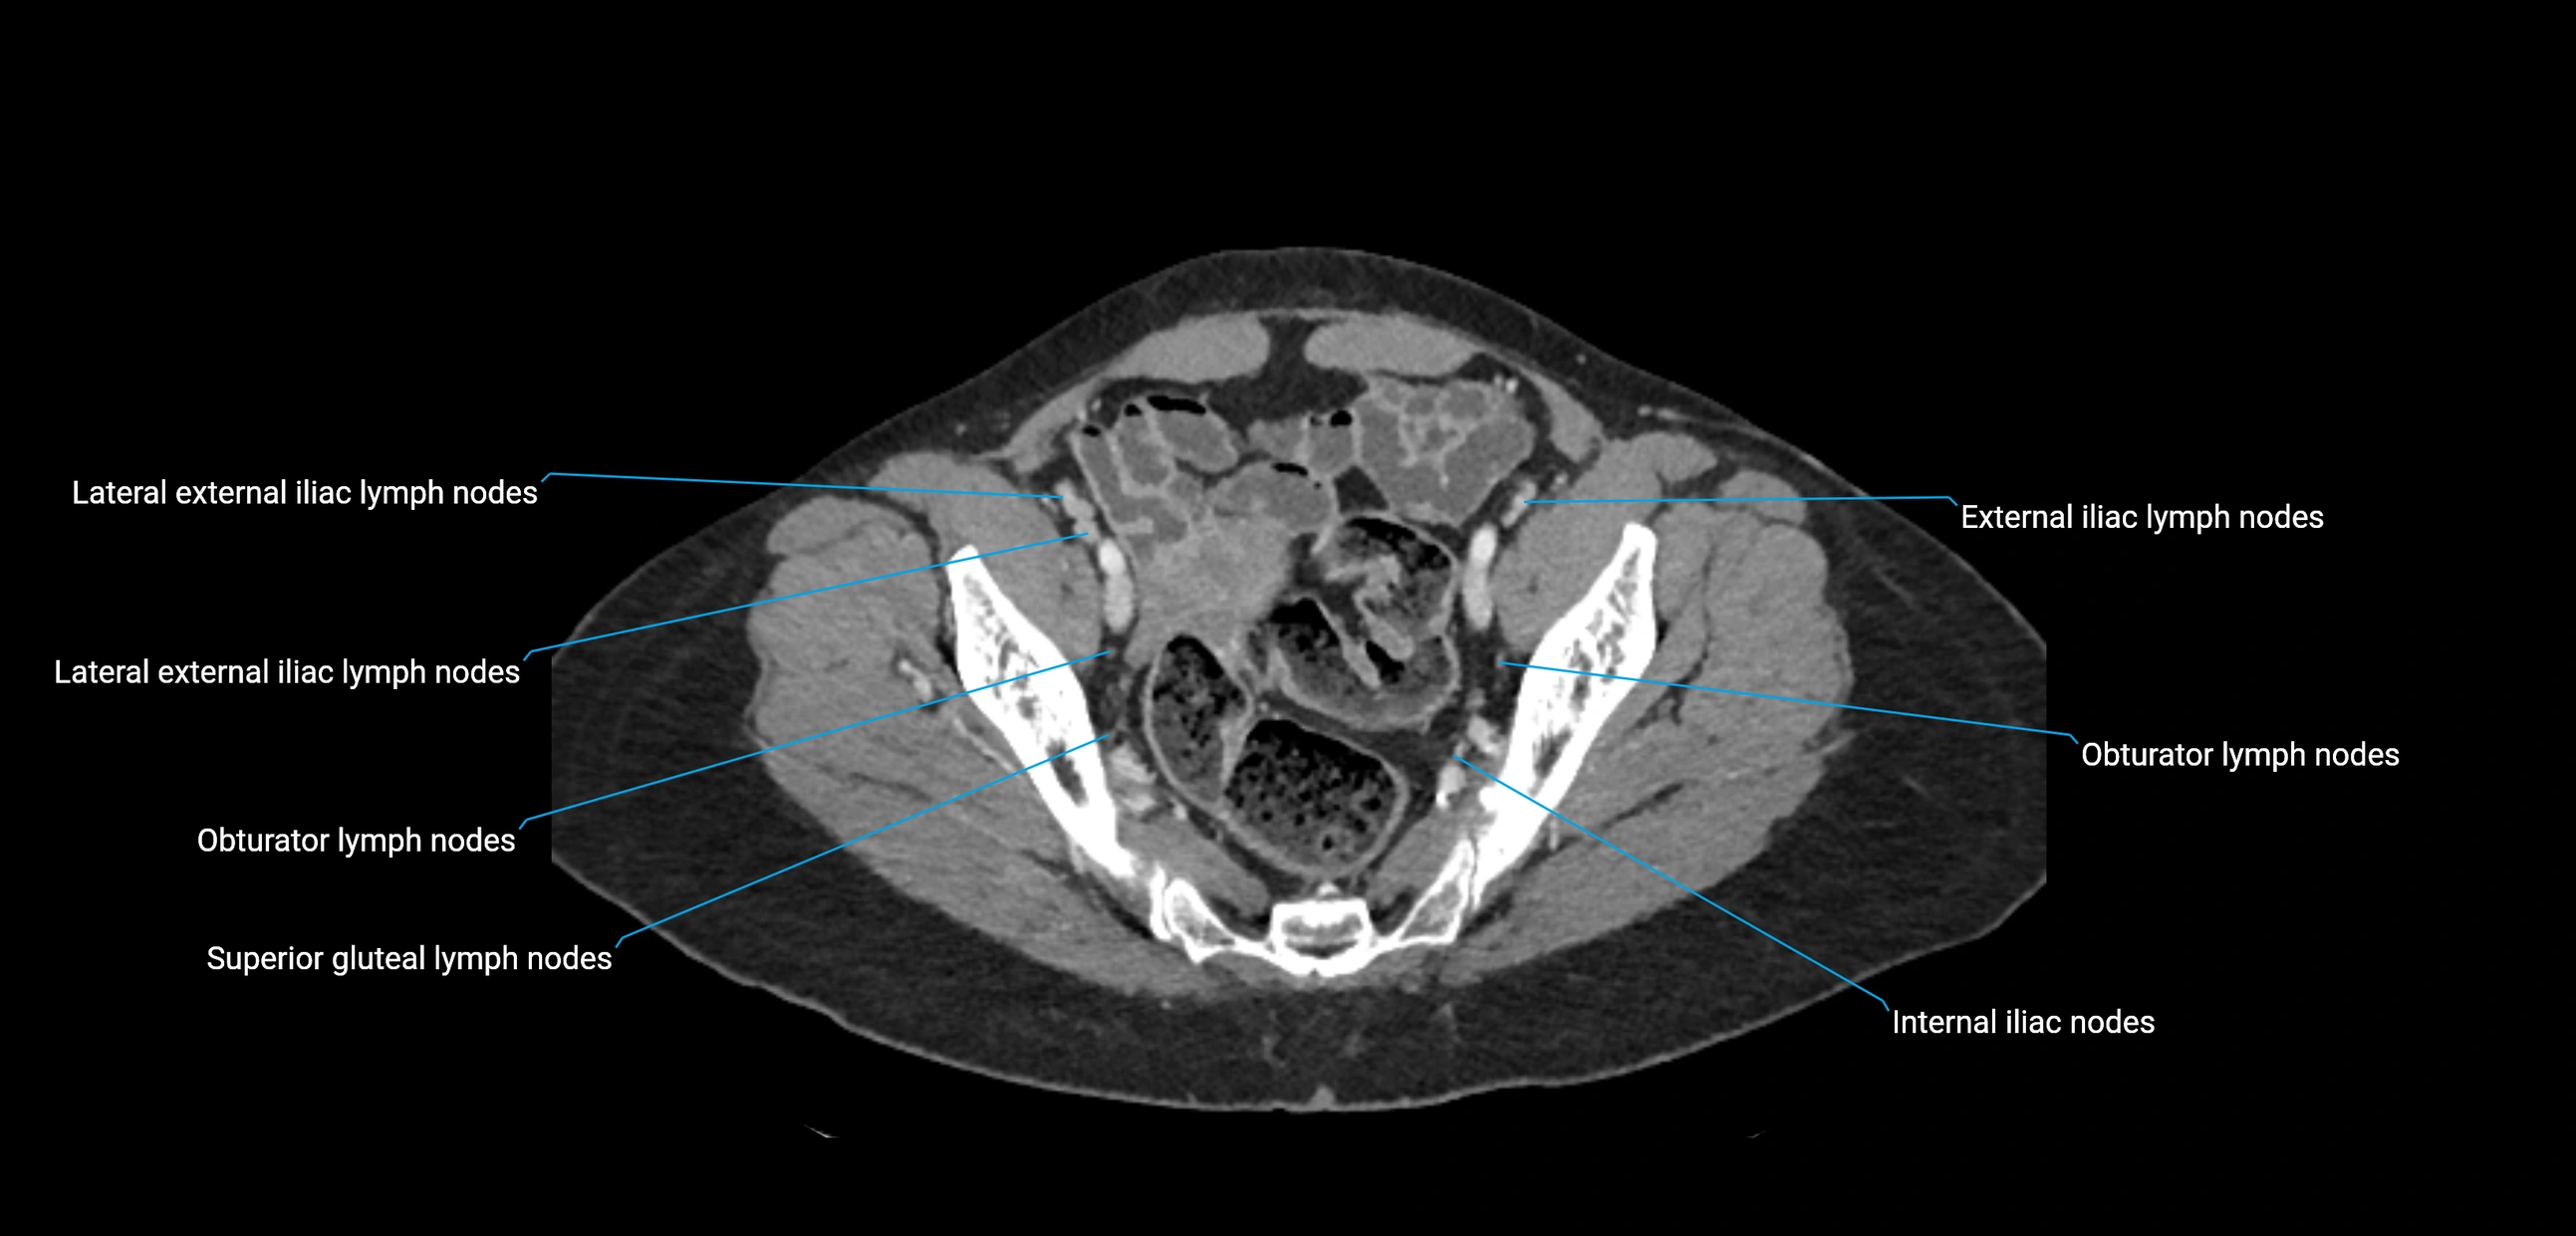

CT Appearance

CT Pre-Contrast:

• Nodes appear as soft-tissue density nodules adjacent to the aorta and IVC

• Calcification may be seen in chronic infections (e.g., tuberculosis)

CT Post-Contrast:

• Normal nodes enhance homogeneously

• Malignant nodes may show heterogeneous enhancement, central necrosis, or conglomerate formation

• Size >1 cm short axis is suspicious, though morphology and distribution are equally important